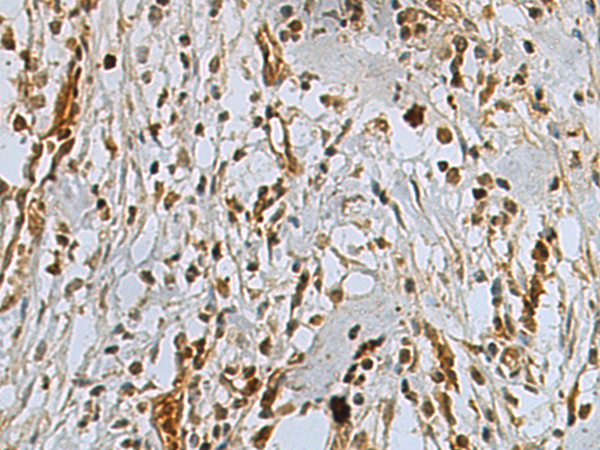

ELISA, IHC |

IHC positive control: |

Human gastric cancer |

IHC Recommend dilution: |

50-200 |